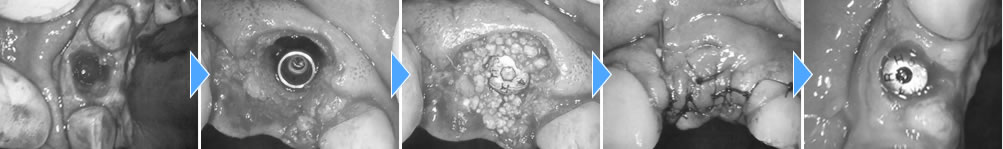

前歯の場合、治療後の歯茎のラインなど審美的に綺麗に行う事も考えて施術を行わないといけません。歯を抜きインプラントを埋入、骨を増やす処置までを1回のオペで行いました。